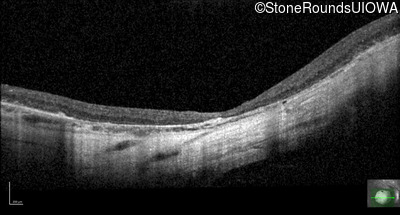

Optical Coherence Tomography - Right - 20/125

Exemplar / OCT Stack

OCT Stack